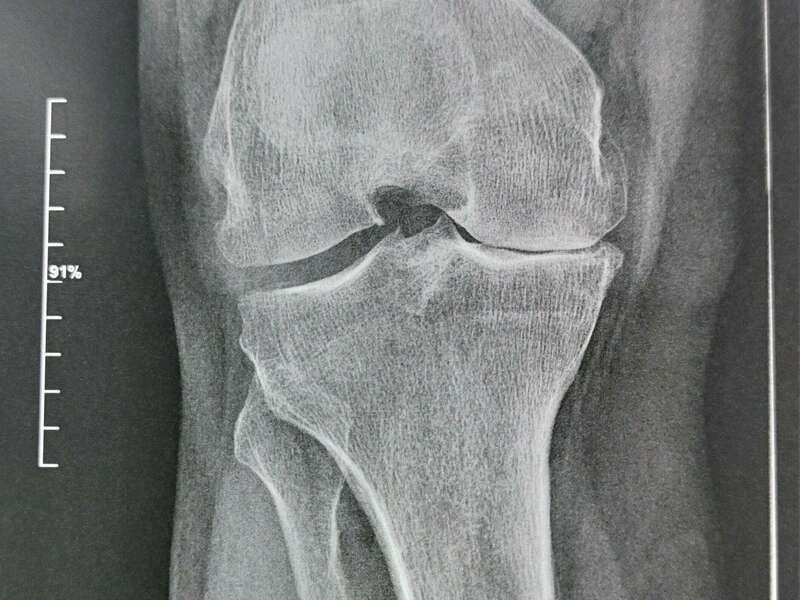

L’articulation du genou assure la jonction entre le fémur (condyles fémoraux), le plateau tibial et la rotule (patella). Elle se compose de deux articulations : l’articulation fémoro-patellaire entre le fémur et la rotule et l’articulation fémoro-tibiale qui elle-même se divise en deux compartiments (interne et externe).

L’ensemble des zones de frottement entre les différents os est recouvert d’un cartilage d’une épaisseur d’environ 3 à 4 mm d’épaisseur qui facilite le glissement entre les différentes surfaces articulaires.

L’arthrose désigne un processus d’usure du cartilage liée au vieillissement. Ce n’est pas une fatalité liée à l’âge. Elle cause des dommages irréversibles du cartilage qui perd au fur et à mesure son rôle de surface de glissement et d’amortisseur. La pression sur l’os s’accroît à mesure que l’épaisseur cartilagineuse diminue.

Des excroissances osseuses, appelées ostéophytes, des kystes osseux et des ulcérations cartilagineuses se forment progressivement. En réponse, la membrane synoviale devient inflammatoire et produit un liquide synovial. L’excès de pression articulaire et l’inflammation sont les causent des douleurs de genou. La perte de congruence de l’articulation entraîne quant à elle, une diminution de la mobilité articulaire.

Elle sera confirmée par des examens radiologiques tels que des radiographies du genou. En cas de doute diagnostic ou afin de rechercher d’éventuelles lésions associées, un scanner et/ou une IRM pourront être prescrits.